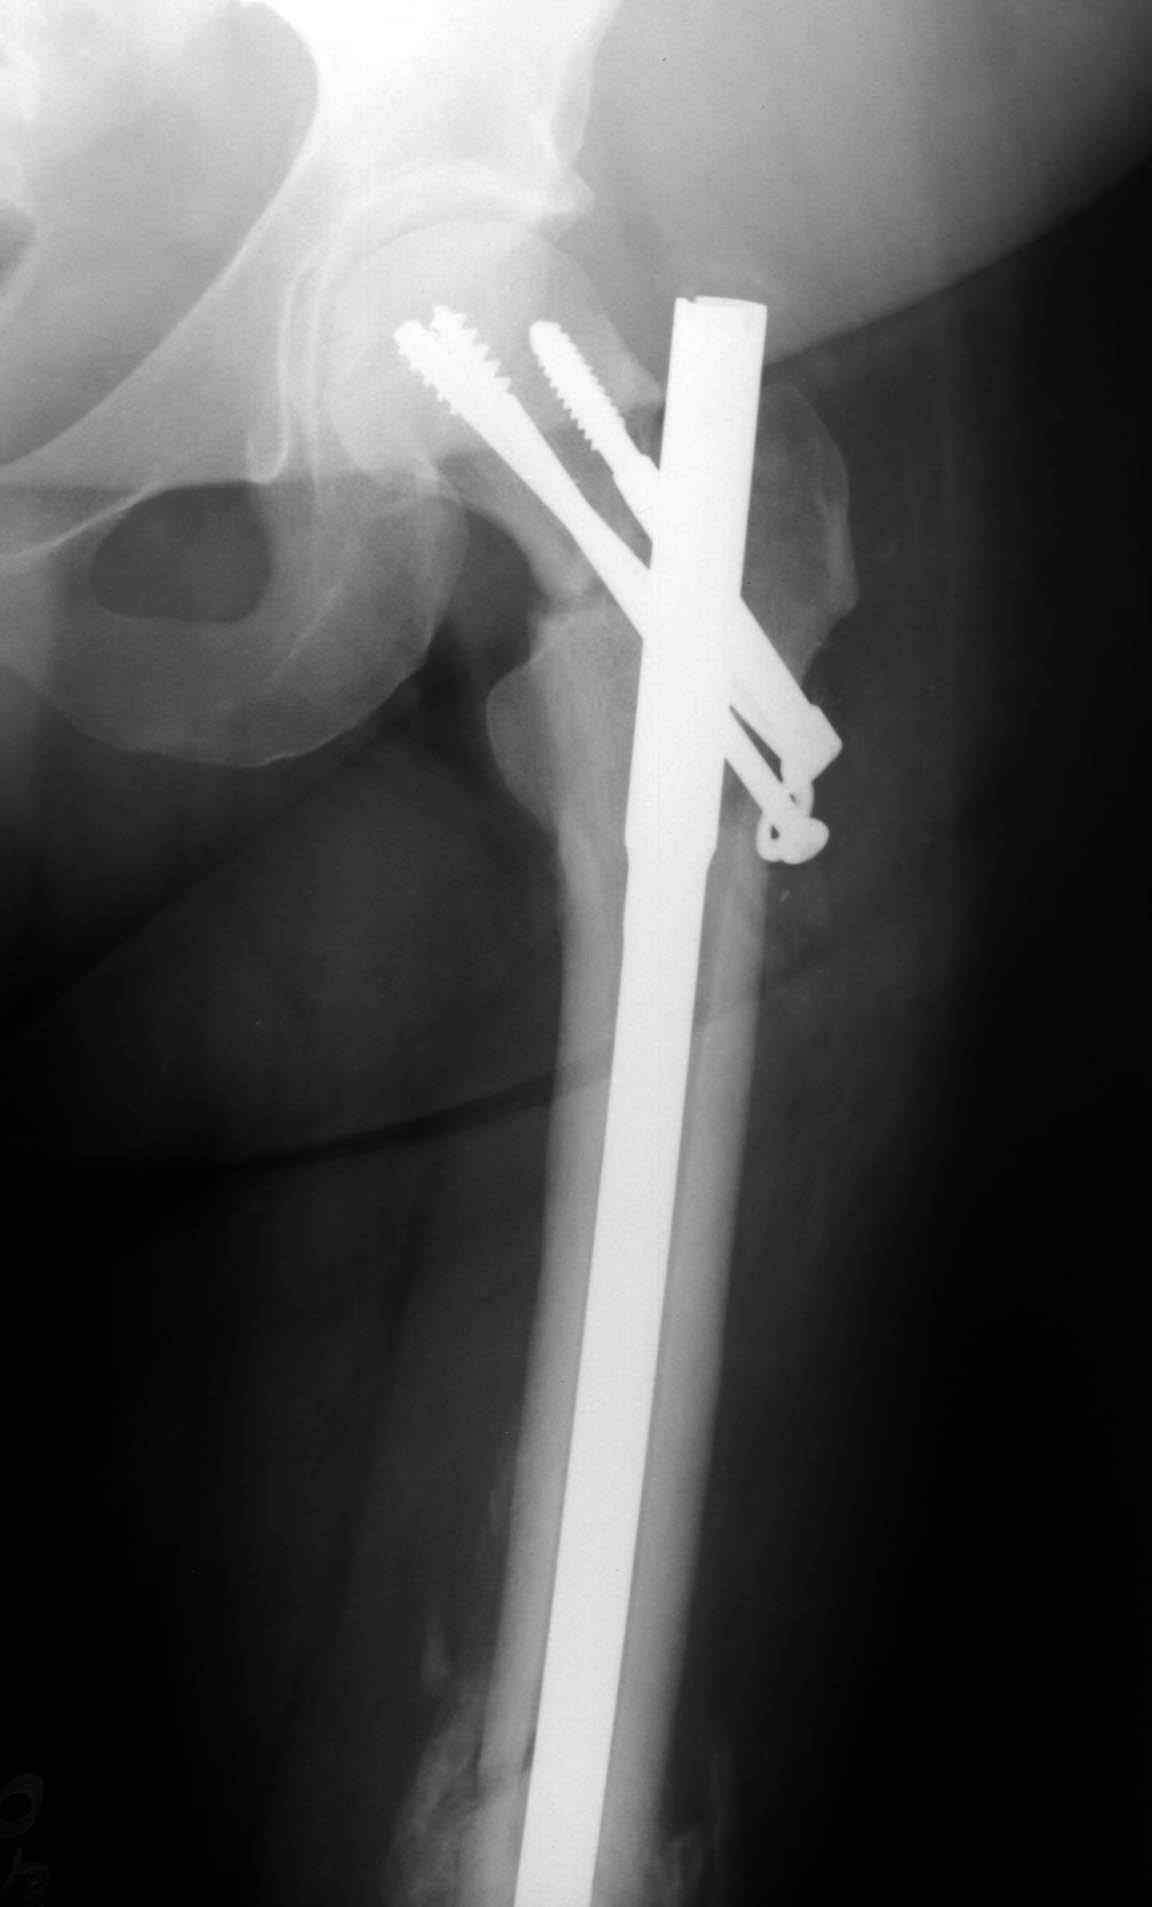

Учитывая молодой возраст больного, из всех рекомендуемых вариантов для лечения ложного сустава шейки предпочтительным является вальгусная остеотомия (на сайте имеются прежние разборы) из-за простоты исполнения и биомехнических преимуществ.

После удаления штифта нет необходимости проведения "стресса" на сращение, лучше провести фиксацию пластиной по два шурупа с каждой стороны.

Минимальный перкутанный доступ без ущерба сохранит сомнительное мозолеобразование и создаст условия для профилактики ложного сустава бедра.

Или при наличии ретроградной техники, короткий штифт с одним блокирующим шурупом дистально, создаст адекватную фиксацию и условия для быстрейшего восстановления.

Несмотря на пессимистические прогнозы, у молодых

коррегирующая вальгусная остеотомия является более

приемлемым.

Представленные случаи доказательства тому, что еще

имеется резервы на восстановление даже у 5-6 месячных ложных суставов шейки.